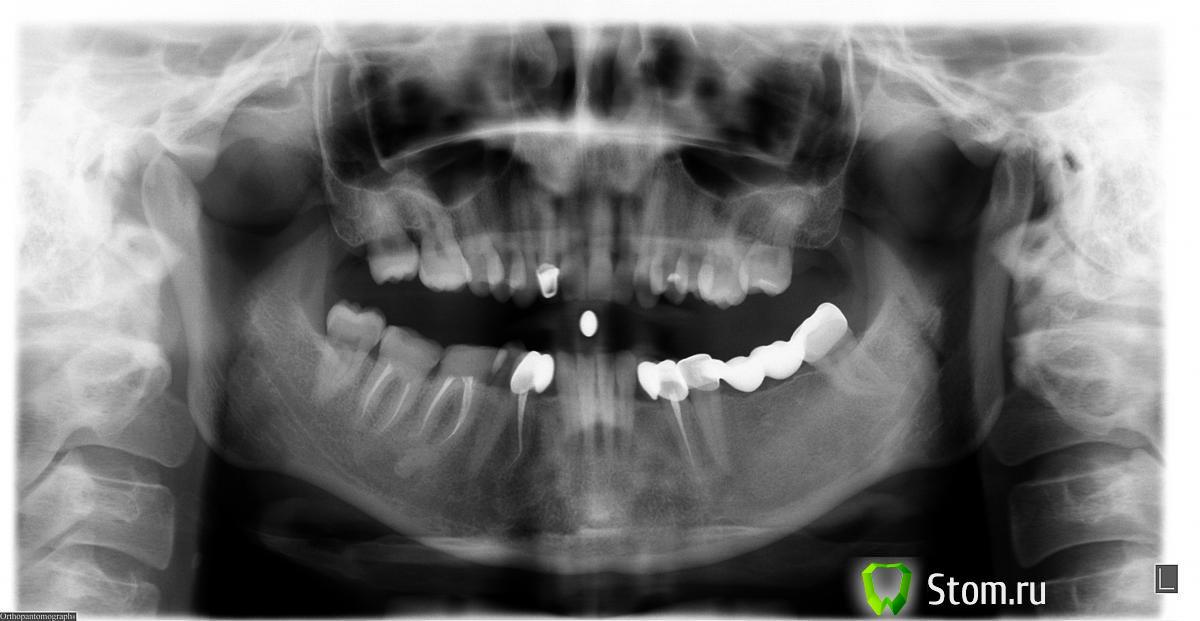

Эндж Опубликовано 1 февраля, 2012 Автор Поделиться Опубликовано 1 февраля, 2012 (изменено) http://s018.radikal....e1b19f8fbab.jpghttp://s017.radikal....61fee8b7b76.jpghttp://s003.radikal....a1508886c89.jpg Добрый день! Прилагаю ТРГ и фото нижнего ряда.На сегодняшний день предложено два варианта лечения:1) Даймон клир или любые железные + 3 микроимпланта. По одному сверху и снизу справа. Доктор говорит, что поставить заваленые зубы без них невозможно. 3-им немного подвинуть левую нижнюю восьмерку, чтобы была полностью в прикусе. Раздвинуть место под клыки для имплантов. Одновременная установка брекетов, микроимплантов и накусочных пломб.2)вариант у другого доктора: Керамика или даймон клир.Для заваленных зубов микроимпланты не нужны. Передвинуть 4-ки нижние на место клыков. Могут, для этой цели понадобится микроимпланты, но могут и не понадобится, будут смотреть, как поведут себя нижние резцы. Так же немного подвинуть нижнюю левую восьмерку какими-то резиками. Установка сначала на верхнюю челюсть, когда немного расширится, на низ.Выскажите, пожалуйста, свое мнение, какой план лечения больше подходит мне? А может Вы бы сделали все по другому? Изменено 1 февраля, 2012 пользователем Эндж Ссылка на комментарий